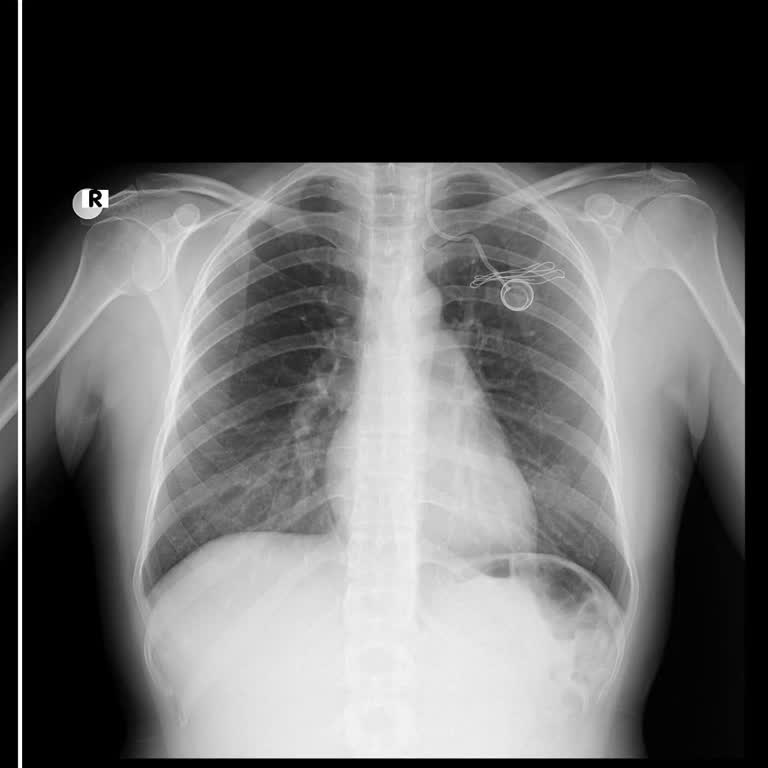

Eşimin meme kanseri tedavisi için geçtiğimiz ay Özel Optimed Hastanesi Çerkezköy Kalp Damar Cerrahisi bölümünde, Prof. Dr. *** tarafından kemoterapi port kateter takılma işlemi yapıldı. “30–40 dakikalık rutin bir işlem” denmesine rağmen eşim operasyon sonrası büyük bir acıyla çıktı. İlk kemoterapi s...